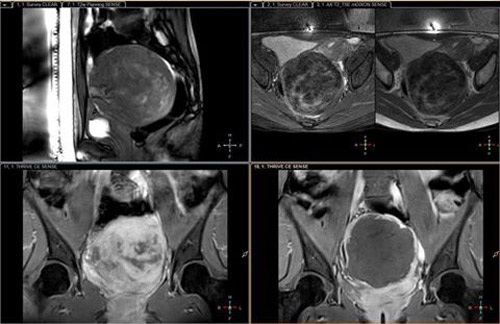

Tại đây, chị được bác sĩ thông báo là có một khối u xơ tử cung khoảng 100mm, chiếm toàn bộ tử cung và phần bụng dưới. Khi siêu âm chị H. đã bị thận ứ nước nặng độ 2 cả hai thận.

Trước đó, bệnh nhân thấy bụng to hơn bình thường nhưng do chủ quan, nghĩ do mình béo bụng nên không đi khám. Khoảng một tháng gần đây, bệnh nhân thấy đau bụng âm ỉ, ra máu âm đạo, không có nhu cầu quan hệ tình dục nên đi khám. Kết quả xét nghiệm, siêu âm cho thấy bệnh nhân bị u xơ tử cung to, khối u có hiện tượng vỡ, gây chảy máu tử cung, phải phẫu thuật cắt bỏ khối u nặng hơn 1 kg.